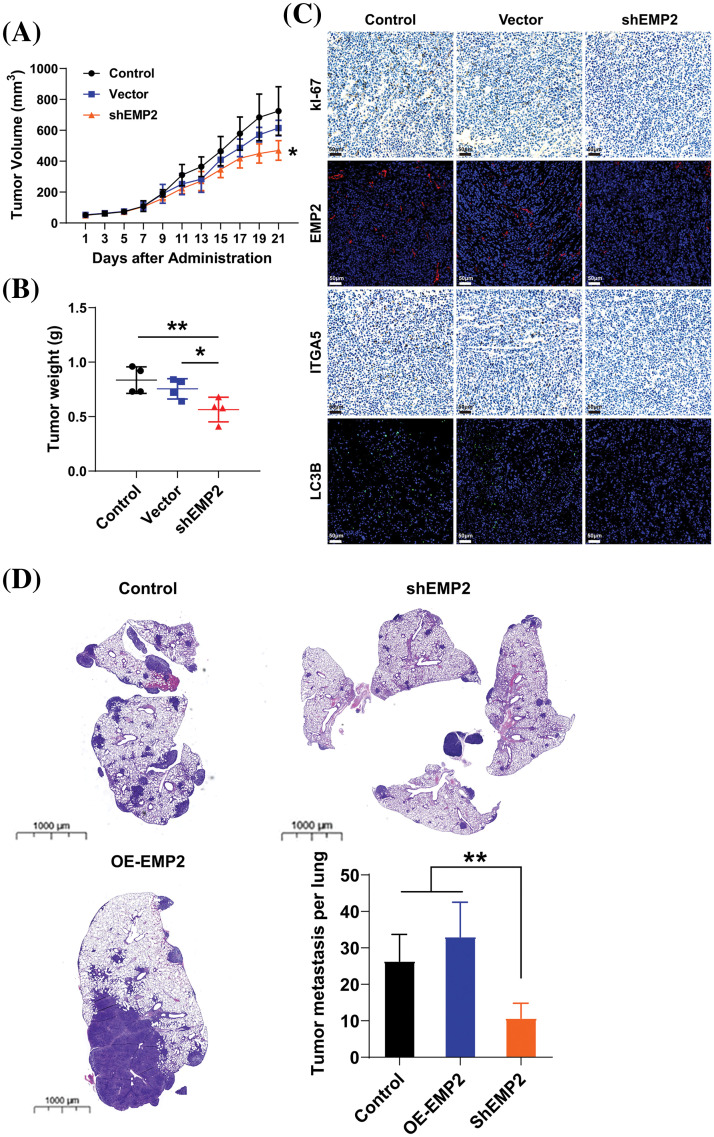

Animal models

All animals were handled according to the animal welfare guidelines and approved by The Ethics Committee of The West China Hospital of Sichuan University (IACUC No. 2021212A). BALB/c nude female mice (6–8 weeks old, weighing 18–20 g) were provided by Beijing Vital River Laboratory Animal Technology Co., Ltd. (China) and reared in the SPF-Class Housing of Laboratory. For the subcutaneous xenograft model, we randomly divided twelve mice into three groups: shEMP2, Vector, and Control (n = 4 mice per group). HepG2 cells stably transfected shEMP2 and shNC, and untreated HepG2 cells (4 × 106) were subcutaneously injected into the ribs of mice. The size of the subcutaneous nodules was measured every 3 days. Tumor tissues were isolated from euthanized mice 4 weeks after inoculation. For the lung metastasis model, HepG2 cells stably transfected shEMP2, HepG2 cells stably overexpressing EMP2 and untreated HepG2 cells (2 × 106) were injected into the tail vein of nude mice (n = 5 mice per group). After inoculation, nude mice were observed daily for health status, including growth and weight, coat color, and appearance. Tumor tissues were isolated from euthanized mice 6 weeks after inoculation. All tissues including tumor tissues, heart, liver, spleen, lungs, and kidneys of mice, were weighed and fixed with formalin for subsequent examinations.

To further evaluate the role of EMP2 in the growth and proliferation capacity of HCC cells, we established shEMP2 stably transfected HepG2 cells for in vivo functional experiments. The results demonstrated a significant inhibition in the growth of HepG2 cells following EMP2 knockdown. Compared to the control group, the EMP2 knockdown group exhibited a significant decrease in tumor growth rate, size, and wet weight (Figs. 8A, 8B). Following 21 days of inoculation, the mice were euthanized, and the intact tumor tissues were embedded and sectioned for immune-histochemical staining of Ki67, EMP2, ITGA5, and LC3B. The results revealed a significant reduction in these markers in the shEMP2 group compared to the control group, indicating a substantial downregulation of EMP2 in the experimental group’s tumor tissues (Fig. 8C). Concurrently, the proliferation capacity of tumor cells decreased, and the expression level of integrin α5 also exhibited a significant decrease. The reduced level of LC3B indicated a decrease in tumor autophagy levels associated with the decrease in EMP2 expression, which is consistent with the in vitro results.